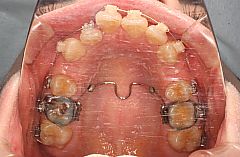

前歯の叢生(でこぼこ)を気にして来院されました。上顎左右側中切歯が典型的な翼状捻転を呈しています。

叢生の程度から判断すると抜歯、非抜歯のボーダーラインケースですが、口唇の突出感が認められたため患者様の意向を加味して上下顎両側の第一小臼歯を抜歯して治療を行うことにしました。

上顎大臼歯が前方に移動することを防止するためにTPA(トランスパラタルアーチ、治療中写真の口蓋を横切る太い針金のことです)を加強固定装置として使用しました。ブラケットは上顎がジルコニア製、下顎は上顎前歯の咬耗を避けるためにコンポジットレジン製のブラケットを使用しています。